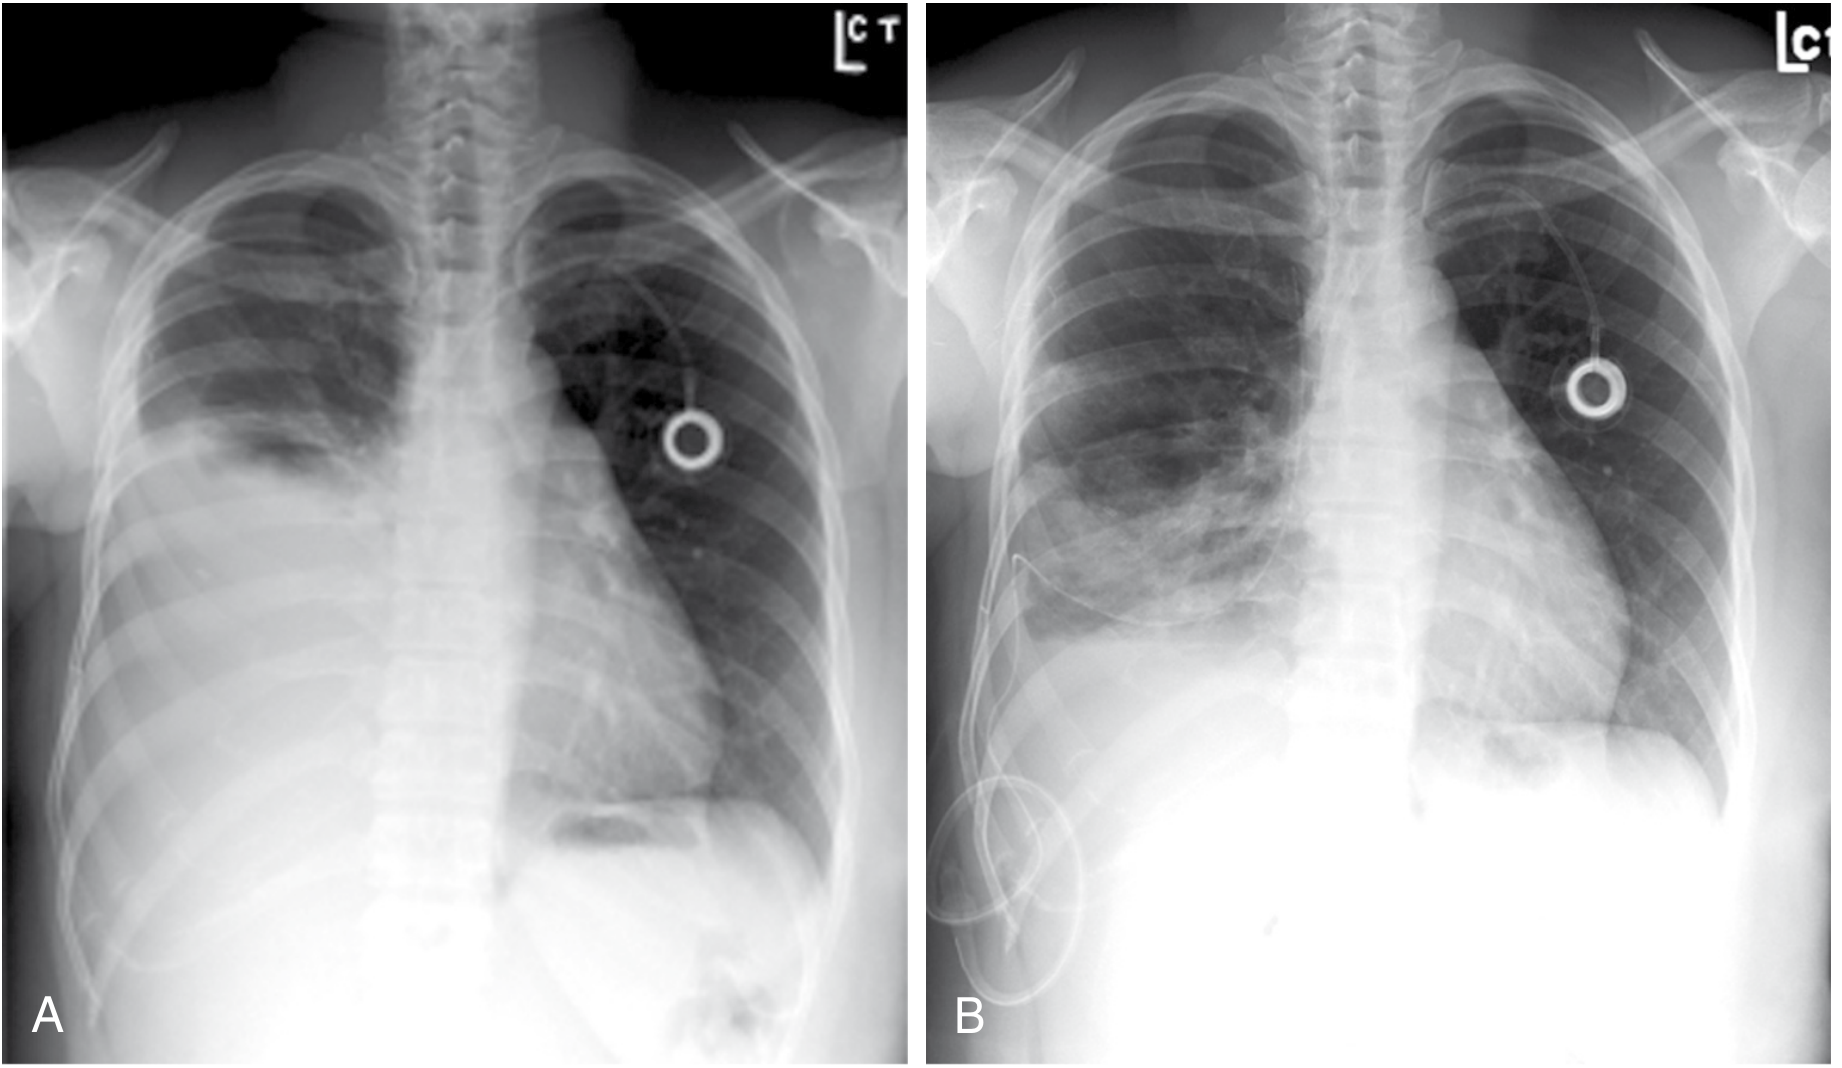

Chest X-rays showing malignant pleural effusion with indwelling pleural catheter in situ (A) and post-drainage with re-expansion (B)

FIGURE: Malignant pleural effusion (A) managed with long-term indwelling pleural catheter for home drainage; (B) post-drainage showing significant lung re-expansion — Sabiston Textbook of Surgery